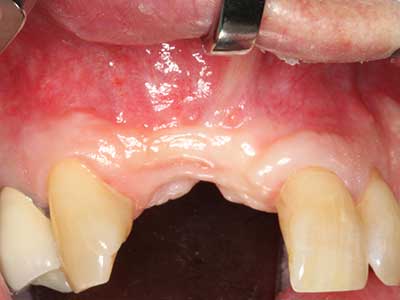

Fig. 16: The intraoral conditions are also stable with embedding of the implants in keratinized gingiva.